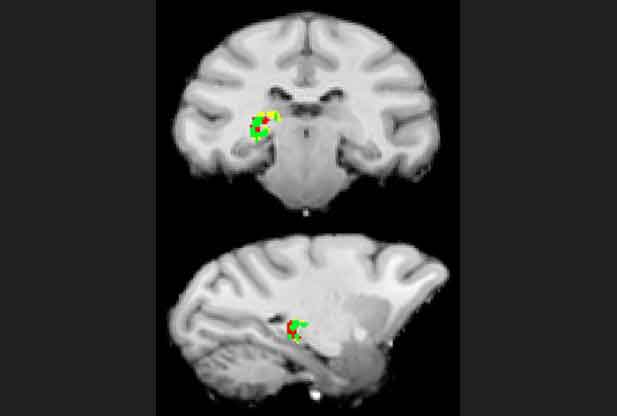

Il nucleo caudato, o pulvinar, uno dei più importanti nuclei del talamo, è coinvolto nella discriminazione visiva tra gli stimoli su cui è fissata l’attenzione e gli elementi di distrazione circostanti: è quanto hanno stabilito Jason Fischer e David Whitney del Dipartimento di Psicologia dell’Università della California a Berkeley, che firmano in proposito un articolo pubblicato sulla rivista “Nature Communications”.

Per colmare questa lacuna, i due ricercatori hanno condotto due esperimenti utilizzando tecniche di imaging a risonanza magnetica funzionale (fMRI) per evidenziare in che modo il pulvinar codifica gli stimoli salienti e i fattori di distrazione quando questi compaiono nello stessa metà del campo visivo del soggetto e quindi sono in competizione tra loro nell’attrarne l’attenzione.

I risulati dei test hanno mostrato che l’attenzione filtra sia le informazioni relative alla posizione sia quelle relative alle caratteristiche intrinseche degli stimoli visivi: la posizione e l’orientamento degli stimoli salienti a cui il soggetto prestava attenzione risultavano codificati con grande precisione, mentre per i fattori di distrazione non emergeva alcuna codifica.

Il risultato indica quindi che il pulvinar è coinvolto nel filtrare l’informazione visiva “di fondo”, aiutando a mantenere la nostra attenzione sugli elementi rilevanti ai fini del comportamento.